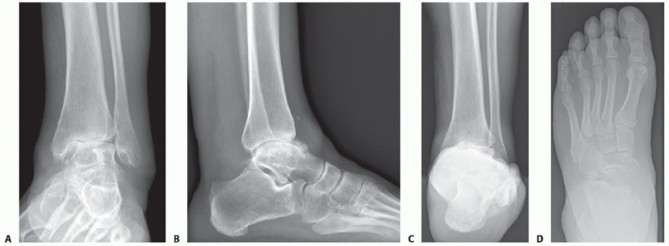

FIG 2 • Preoperative assessment includes weight-bearing standard radiographs as follows: (A) AP view of the ankle, (B) lateral view of the foot, (C) Saltzman alignment view, and (D) AP view of the foot.*

Plain weight-bearing radiographs, including anteroposterior (AP) views of the foot and ankle, a lateral view of the foot, and an alignment view of the hindfoot6 (FIG 2), are obtained to assess the following:

Extent of destruction of the tibiotalar joint (eg, tibia, talus, and fibula) Status of neighboring joints (eg, associated degenerative disease)

Deformities of the foot and ankle complex (eg, heel alignment, foot arch, talonavicular alignment) Tibiotalar malalignment (eg, varus, valgus, recurvatum, and antecurvatum)

Bony condition (eg, avascular necrosis, bony defects)